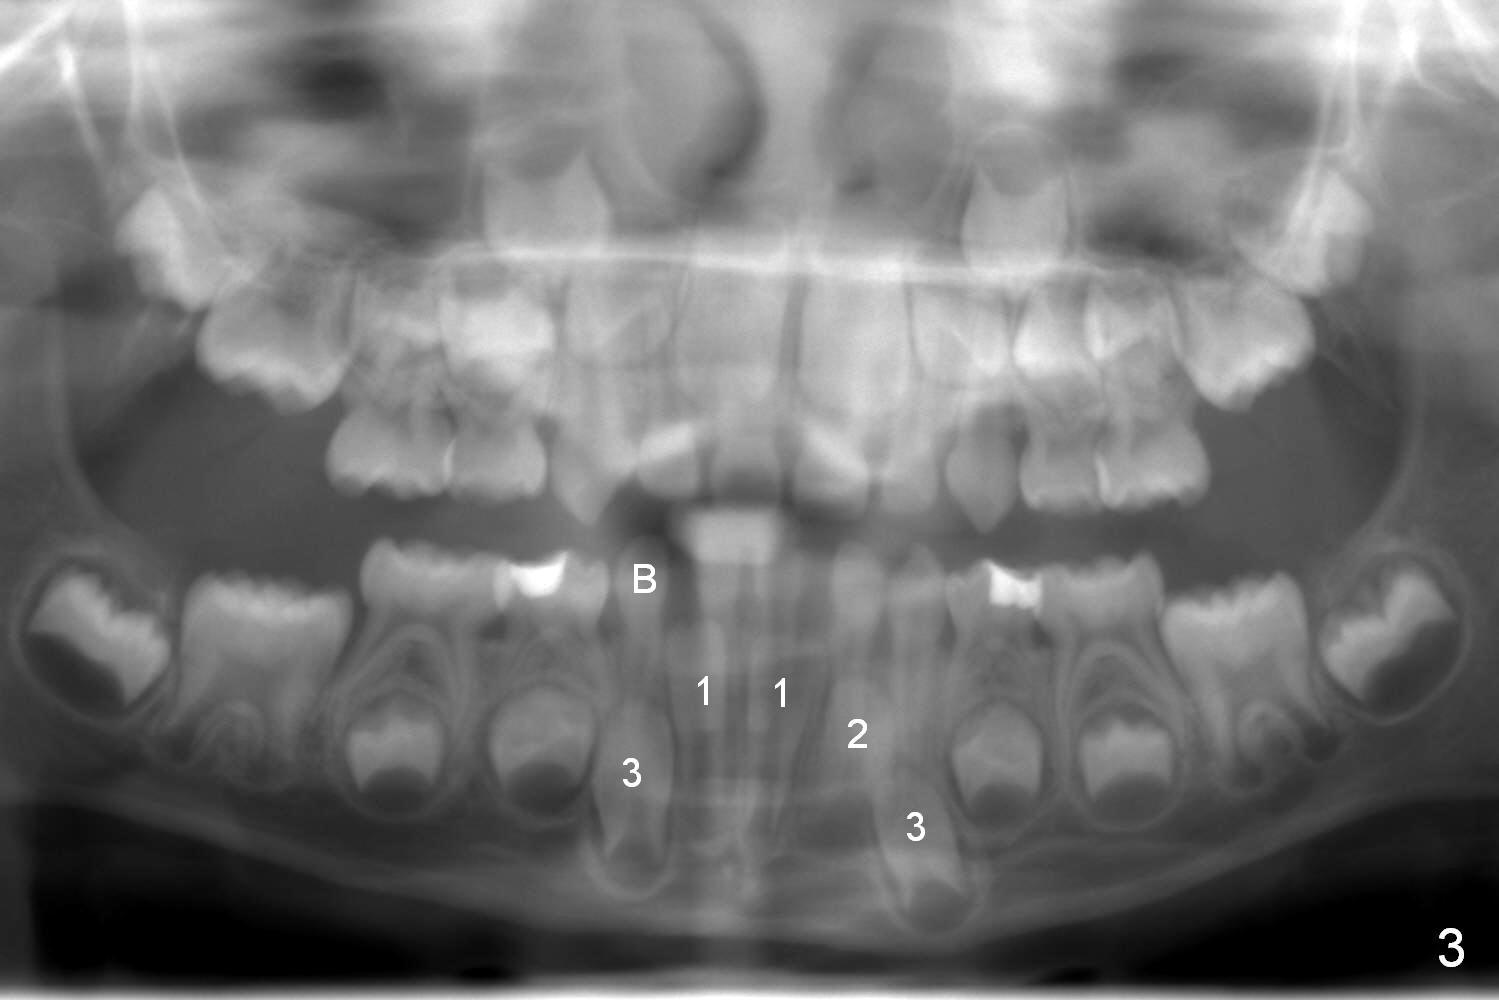

When a 6-year-4-month-old Oriental boy (XA) presents for new patient exam, the lower right (LR) deciduous canine (C) is found missing (Fig.1,2). The LR lateral incisor (B) is at the position of C. Which of the underlying permanent teeth is missing, lateral or canine?

As is known, the deciduous tooth buds give rise to the underlying permanent ones (Fig.4 (illustration for the anterior teeth). Where LR C is missing, most likely the permanent canine (LR 3) is missing (Fig.5,6), whether B is shifted or not.

In fact, in this case, the lateral incisor (LR 2) is missing (Fig.3, 7).